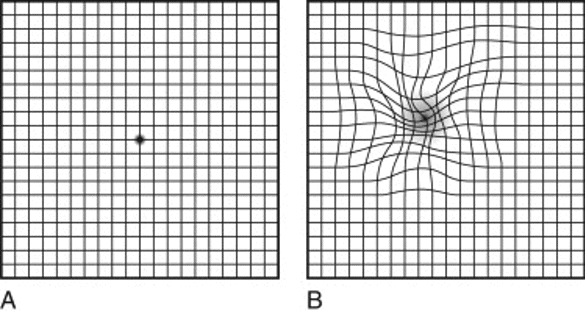

What are the symptoms of macular edema?

- Blurry or wavy vision near or in the center of your vision.

- Colours might also appear washed out or faded.

- If only one eye is affected, you may not notice your vision is blurry until the condition is more serious

Amsler grid can be used to test your central vision. Covering one eye to test each eye. Look at the black dot at reading distance. If the lines appear wavy, you may have a macular problem (Image B).